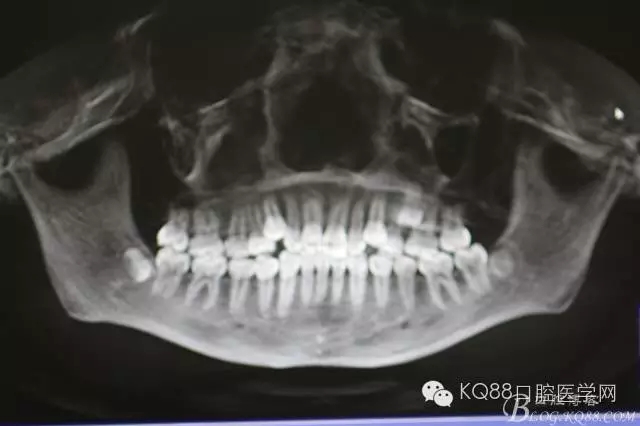

患者、常xx、男、15歲,主訴:牙齒排列不齊,要求正畸治療。??茩z查:25口內(nèi)未見萌出,24與26鄰接正常,CBCT檢查:25腭側(cè)埋伏阻生,正畸科建議拔除25,患者家屬同意正畸治療方案,簽知情同意書。遂轉(zhuǎn)外科拔除埋伏的25.

圖1.術(shù)前口內(nèi)頰側(cè)觀:24與26鄰接正常,頰側(cè)黏膜平整、無隆起。

圖3.術(shù)前的CBCT檢查:全景片重建影像,25位于24與26牙根的中1/3處。